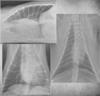

Q

DV

VD